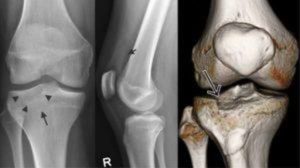

Довольно точную картину поражения можно увидеть при помощи рентгена, который делается в двух проекциях (прямо и боком).

Это позволяет увидеть наличие трещины, перелома, степени смещения мыщелков с деформацией, а также возможные нарушения других структур и тканей в области коленного сустава.

При вдавленном переломе используется снимок суставной площадки. Для определения протяженности перелома назначаются снимки в косой проекции.

Обычно проведения рентгеновской диагностики бывает достаточно для уточнения диагноза. Если по какой-то причине ее результаты не устраивают специалиста, то более точную картину патологии можно получить с помощью КТ или МРТ. Эти исследования помогают диагностировать скрытые формы переломов и разрывы связок.

Если перелом проходит через оба мыщелка, то такое отклонение называется чрезмыщелковым переломом. Компрессионная форма (сдавление) выглядит при исследовании неровной линией с множественными обломками. Импрессионный перелом латерального мыщелка большеберцовой кости или медиального, который переводится как «вдавленный» может сочетаться с компрессионным.

Основным методом инструментальной диагностики является рентгенография коленного сустава. Рентгеновские снимки выполняют в двух проекциях. В абсолютном большинстве случаев это позволят достоверно установить не только факт наличия переломов, но и характер смещения отломков. При неоднозначных результатах рентгенографии пациента направляют на КТ сустава.

При подозрении на сопутствующее повреждение мягкотканных структур (связок или менисков) назначают МРТ коленного сустава. Иногда переломы мыщелков сопровождаются сдавлением нервов и сосудов, при подозрении на повреждение сосудисто-нервного пучка (повреждение сосуда и повреждение нерва) назначают консультации сосудистого хирурга и нейрохирурга.